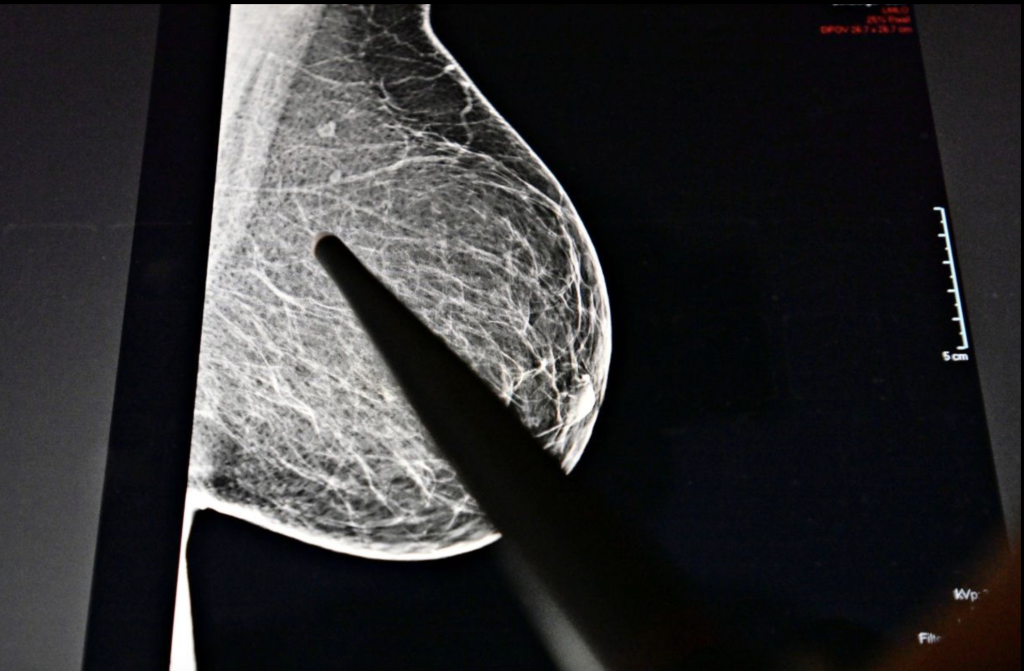

Großes Problem sei die Früherkennung. Besser gesagt, die nicht vorhandene Früherkennung. Denn routinemäßige Mammografie-Screeningprogramme werden Frauen ab 45 Jahren empfohlen, jüngere sind üblicherweise nicht die Zielgruppe für Früherkennungsmaßnahmen.

Dass hier raschest möglich ein Umdenken stattfinden muss, zeigt auch eine neue US-Studie, die am Montag auf der Jahrestagung der Radiological Society of North America (RSNA) vorgestellt wurde. Ziel der Studie war es herauszufinden, wie häufig Brustkrebs unter jungen Frauen auftritt, in welchem Stadium sich die Tumoren befinden und wie sie entdeckt wurden. Dafür analysierte das Team die Daten von sieben ambulanten Einrichtungen im Umkreis von New York. Mit dem Ergebnis: Zwischen 2014 und 2024 wurden insgesamt knapp 1800 Brustkrebsfälle bei Frauen im Alter von 18 bis 49 Jahren diagnostiziert. Das waren jährlich zwischen 20 und 24 Prozent aller Brustkrebsfälle – also fast ein Viertel aller Brustkrebspatientinnen sind bereits unter 49 Jahre alt. "Diese Studie zeigt, dass ein erheblicher Anteil der Krebserkrankungen bei Frauen unter 40 diagnostiziert wird, einer Gruppe, für die es derzeit keine Vorsorgerichtlinien gibt", erklärt dazu die Radiologin Stamatia Destounis.